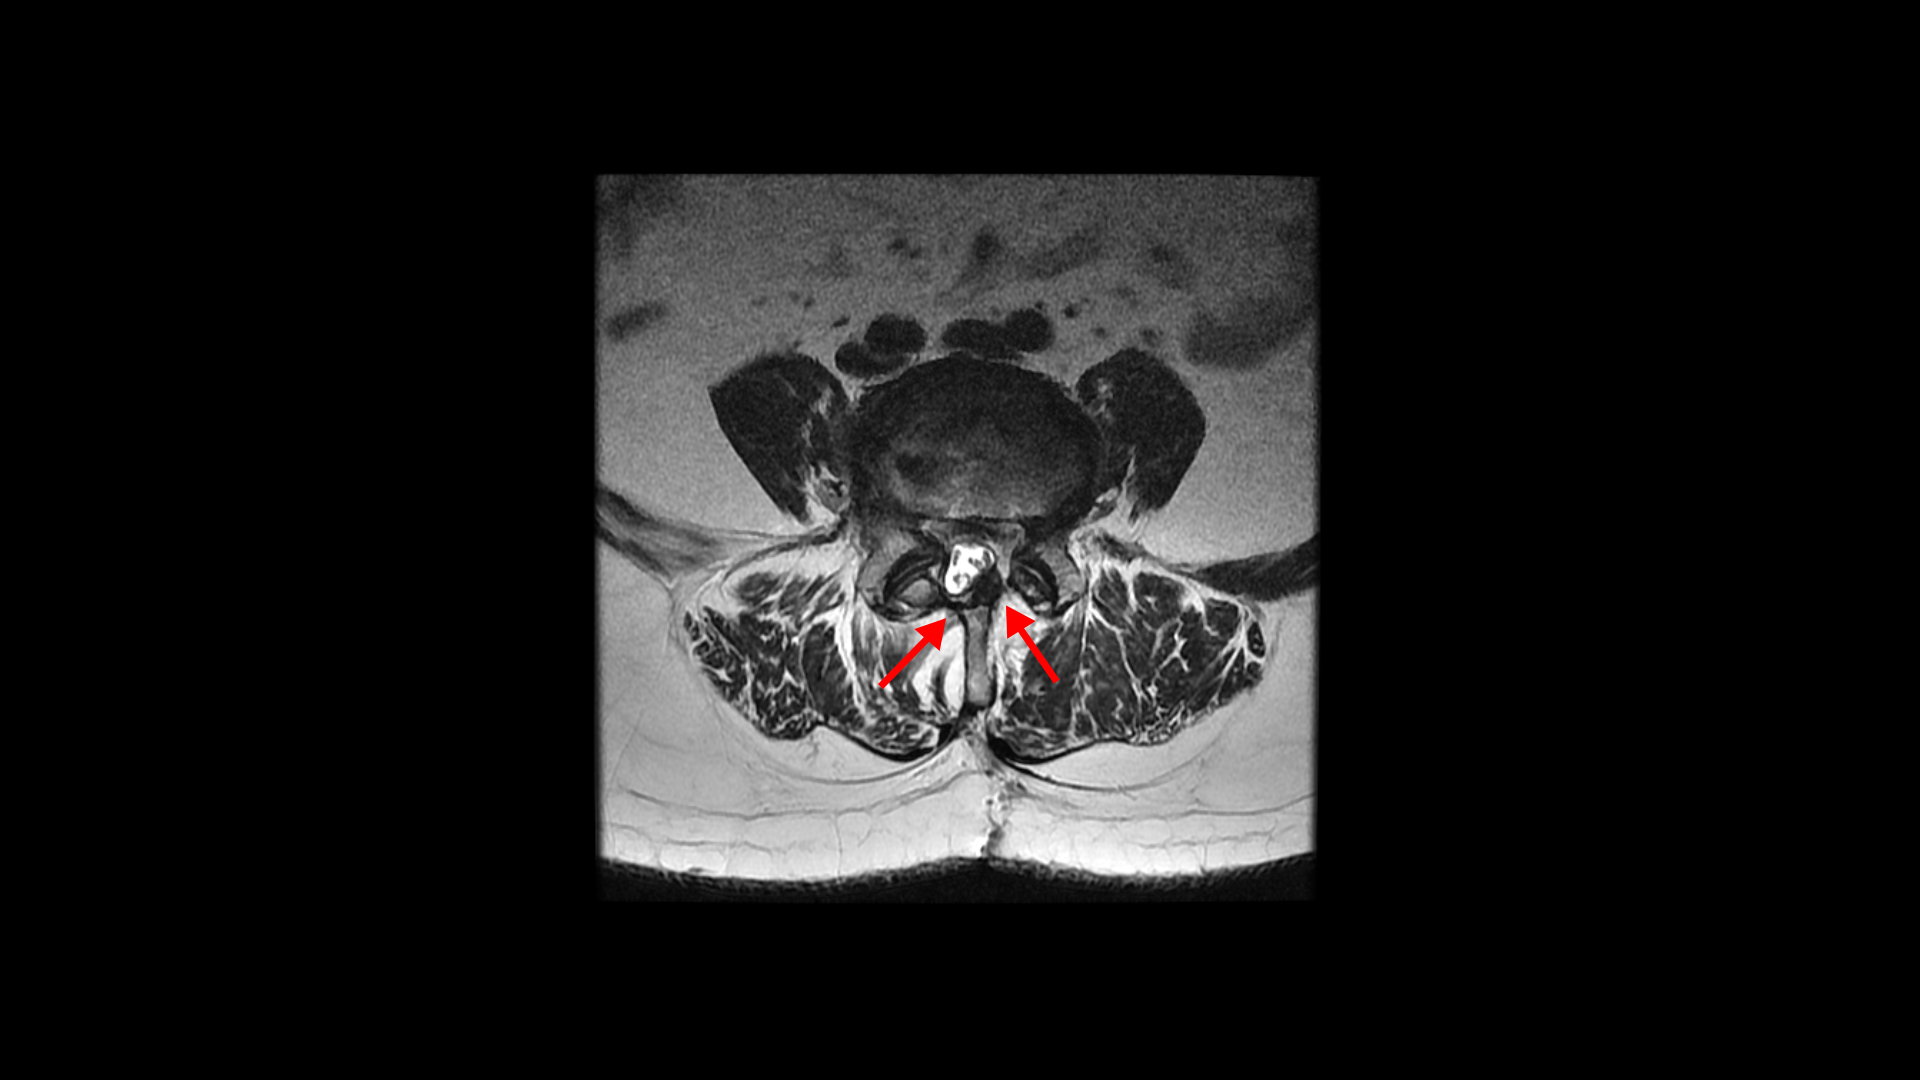

올해 초에 디스크가 4번 5번에서 또 오른쪽으로 심하게 터져서 결국은 후궁과 후관절, 황색인대를 모두 다 제거하고 나사를 박는 유합술을 하셨습니다.

그런데 유합술 후 오른쪽 다리의 증상은 좋아졌으나 상대적으로 괜찮았던 왼쪽 다리에 심한 방사통과 마비 증상이 생겼습니다. 수술 후에 집도의로부터 수술은 잘 됐으나 수술한 자리가 부어있어서 신경을 눌러서 그럴 거니까. 1년 이상 기다리면 좋아질 것이라는 얘기를 들었습니다. 그런데 저희 모커리한방병원은 디스크나 협착증, 전방전위증 등으로 오랫동안 다리 방사통을 겪은 환자분들 중 수술받은 분들께 수술 후 남아있거나 새로 생기는 방사통이나 마비 증상은 회복을 위해 1년씩 혹은 그 이상 오래 기다릴 필요가 없다고 말씀 드리고 있습니다. 보통은 수술집도의 분들의 설명은 수술 전에 오래 눌려있던 신경이 다시 회복되는데 시간이 오래 걸리기 때문에 기다려야 한다고 얘기하는데, 저희 관점에서는 척추 수술 후 회복되는데 시간이 오래 걸리는 이유가 전혀 다릅니다.

실제로 수술을 잘해서 눌린 신경을 성공적으로 잘 풀어준 후에도 통증이나 마비가 남아있거나 안 아프던 다리에 통증이 새로 생기는 환자들이 많습니다. 그런데 다시 말씀 드리지만 수술 전 근육의 문제가 전혀 해결되지 않은 상태에서 수술을 하면 눌린 신경은 풀어주지만, 근육의 문제는 전혀 해결이 안 된 상태이고 또 수술 시 근육의 일부를 찢고 자르면서 근육에는 추가적인 손상을 주게 되니까 근육 문제는 오히려 더 심해질 수도 있습니다. 그래서 수술 후에도 다리 저림이나 마비 증상이 남아있거나 없던 증상이 새로 생길 수 있는 겁니다.